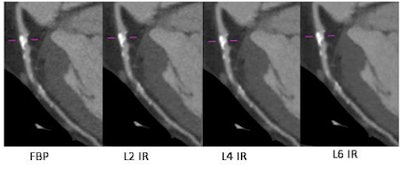

"The aim of this study was to compare coronary plaque size and composition as well as the degree of coronary artery stenosis on CCTA [coronary CT angiography] using three different levels of iterative reconstruction [IR] and filtered back projection [FBP]," he said.

The study team analyzed 63 patients (45 men, 18 women, mean age 50.8 ± 13.0 years) who underwent CCTA using a step-and-shoot protocol on a 256-detector-row scanner (Brilliance iCT, Philips Healthcare). Takx and colleagues Dr. Martin Willemink, Dr. Arnold Schilham et al reconstructed the raw CT data using FBP and three different levels (2, 4, 6) of the IR reconstruction algorithm (iDOSE 4, Philips Healthcare).

However, image quality improved dramatically, mostly owing to noise reduction. Image noise fell by 42% (p < 0.0001), while SNR in the aorta rose by 72.5% (p < 0.001) and CNR by 72.0% when iterative reconstruction was dialed up to level 6, for example.